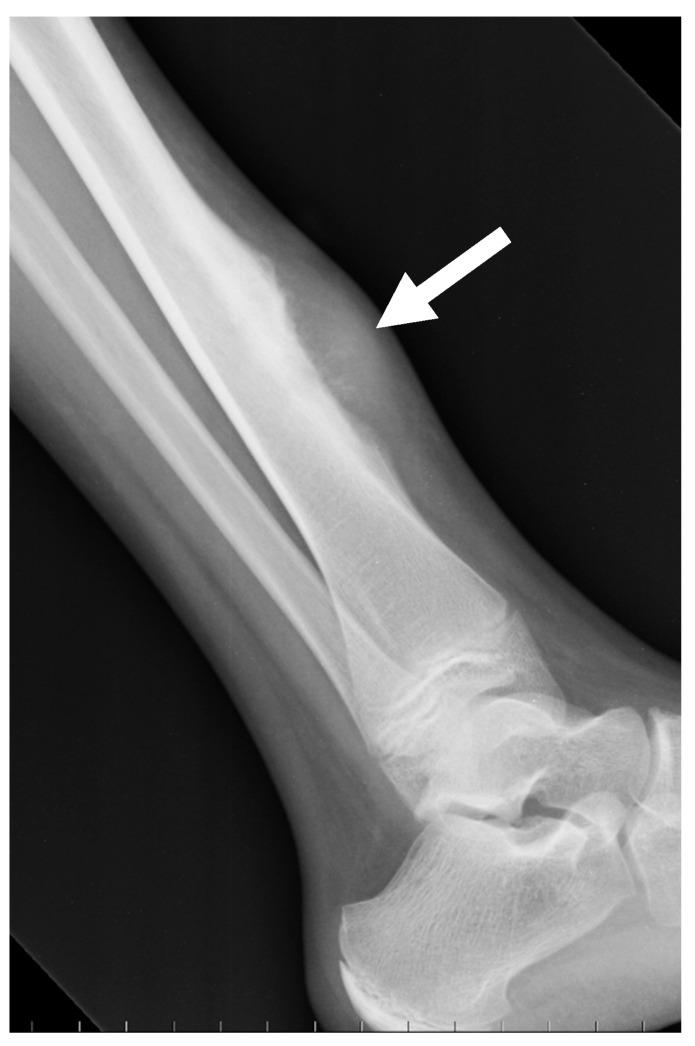

Osteosarcomas are rare malignancies (<1% of all cancers) that produce an osteoid matrix. Osteosarcomas are the second most frequent type of primary bone tumor after multiple myeloma and the most prevalent primary bone tumor in children. The spectrum of imaging findings of these malignancies varies significantly, reflecting different histological subtypes. For instance, conventional osteosarcoma typically presents with a mixed radiological pattern (lytic and bone mineralization) or with a completely eburneous one; aggressive periosteal reactions such as sunburst, Codman triangle, and soft-tissue components are frequently displayed. On the other hand, telangiectatic osteosarcoma usually presents as a purely lytic lesion with multiple fluid-fluid levels on MRI fluid-sensitive sequences. Other typical and atypical radiological patterns of presentation in other subtypes of osteosarcomas are described in this review. In addition to the characteristics associated with osteosarcoma subtyping, this review article also focuses on imaging features that have been associated with patient outcomes, namely response to chemotherapy and event-free and overall survivals. This includes simple semantic radiological features (such as tumor dimensions, anatomical location with difficulty of radical surgery, occurrence of pathological fractures, and presence of distant metastases), but also quantitative imaging parameters from diffusion-weighted imaging, dynamic contrast-enhanced MRI, and 18F-FDG positron emission tomography and radiomics approaches. Other particular features are described in the text. Overall, this comprehensive literature review aims to be a practical tool for oncologists, pathologists, surgeons, and radiologists involved in these patients' care.

骨肉瘤是一种罕见的恶性肿瘤(占所有癌症的比例不到1%),可产生类骨质基质。骨肉瘤是继多发性骨髓瘤之后第二常见的原发性骨肿瘤类型,也是儿童中最常见的原发性骨肿瘤。这些恶性肿瘤的影像学表现谱差异很大,反映了不同的组织学亚型。例如,传统骨肉瘤通常表现为混合性放射学模式(溶骨性和骨矿化)或完全骨化模式;常显示侵袭性骨膜反应,如日光放射状、科德曼三角和软组织成分。另一方面,毛细血管扩张性骨肉瘤通常表现为纯溶骨性病变,在MRI液体敏感序列上有多个液-液平面。本文综述了骨肉瘤其他亚型的其他典型和非典型放射学表现模式。除了与骨肉瘤亚型相关的特征外,本文还重点关注与患者预后相关的影像学特征,即对化疗的反应、无事件生存期和总生存期。这包括简单的语义放射学特征(如肿瘤大小、根治性手术困难的解剖位置、病理性骨折的发生以及远处转移的存在),也包括扩散加权成像、动态对比增强MRI、18F-FDG正电子发射断层扫描和放射组学方法的定量成像参数。文中还描述了其他特殊特征。总体而言,这篇全面的文献综述旨在成为参与这些患者护理的肿瘤学家、病理学家、外科医生和放射科医生的实用工具。